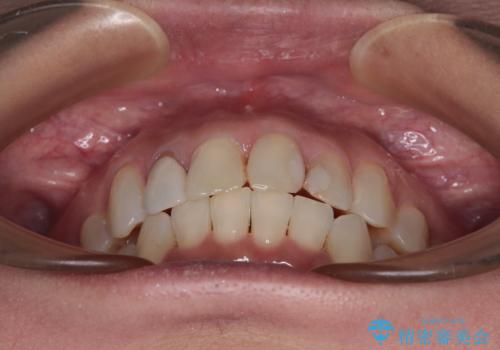

前歯のデコボコとむし歯治療の跡 インビザライン矯正とオールセラミッククラウン治療

- 前歯のセラミッククラウンの縁が見えることが気になってから、デコボコも気になるようになってきたとのことで来院された患者様です。

デコボコの程度は中等度であったため、インビザライン・モデレートパッケージにて歯列を整えることとしました。

セラミッククラウンの装着されていた前歯と、大きな修復治療の跡がある反対側の歯は、矯正治療後に補綴治療を行うこととしました。

奥歯の欠損はインプラント、ブリッジ、入れ歯のどれにすれば良いかを決められず、仕事が非常にお忙しいこともあり、保留としたまま治療を終えることとなりました。

後戻りのリスクがあるため、なるべく早めに欠損補綴治療を開始する予定です。